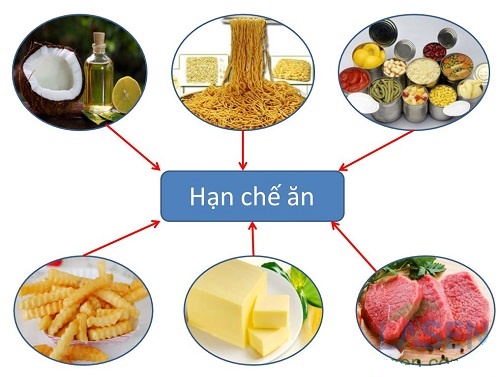

- Mỡ máu tăng cao do chế độ ăn quá nhiều chất béo:

Ăn quá nhiều chất béo bão hòa có thể khiến mức cholesterol tăng gây ra mỡ máu cao. Các loại thực phẩm có hàm lượng chất béo bão hòa cao như thịt bò, thịt lợn, thịt bê, sữa, trứng. Thực phẩm đóng gói, đồ hộp chứa dầu dừa, dầu cọ, bơ ca cao cũng có thể chứa hàm lượng chất béo cao.

2. Cao mỡ máu không nên ăn gì?

Bệnh mỡ máu cao là tình trạng dư thừa lượng chất béo không cần thiết trong cơ thể, là nguyên nhân gây nên nhiều căn bệnh khác nhau và nếu không có cách điều trị kịp thời thì tính mạng dễ rơi vào tay tử thần. Như đã nói ở trên, điều trị mỡ máu cao phải xuất phát từ ăn uống, bệnh mỡ máu kiêng ăn gì? Khi mắc phải căn bệnh này, bạn cần hạn chế sử dụng các thực phẩm sau đây:

Thực phẩm người bị cao mỡ máu không nên ăn

- Hạn chế sử dụng mỡ động vật (mỡ lợn, mỡ bò, mỡ gà, bơ,..):

Trong mỡ động vật chứa các loại chất béo no, khó tan, nếu sử dụng nhiều sẽ làm tắc các động mạch ảnh hưởng đến quá trình truyền máu trong cơ thể. Chỉ nên sử dụng < 30% calo/ngày.

- Hạn chế các đồ ăn nhanh:

Các đồ ăn nhanh sử dụng rất nhiều dầu mỡ để chiên rán, đặc biệt là việc sử dụng dầu chiên rán lại nhiều lần vừa không đảm bảo vệ sinh vừa làm tăng lượng mỡ thừa có hại cho cơ thể.

- Không nên ăn các loại đồ ăn có chứa thành phần đạm vào buổi tối:

Buổi tối là lúc cơ thể ta tiêu hao rất ít năng lượng nên nếu nạp vào cơ thể nhiều năng lượng không tiêu thụ hết sẽ tích tụ lại, đồng thời đạm là chất khó tiêu nên khi ăn vào buổi tối nó sẽ tích tụ lại trên các động mạch gây nên tắc nghẽn mạch máu và xơ vữa động mạch.

- Kiêng các loại đồ ăn có đường:

Khi ăn quá nhiều những loại đồ ăn chứa đường sẽ là một trong những nguyên nhân gây nên tình trạng thừa cân, một yếu tố dẫn đến bệnh mỡ máu.